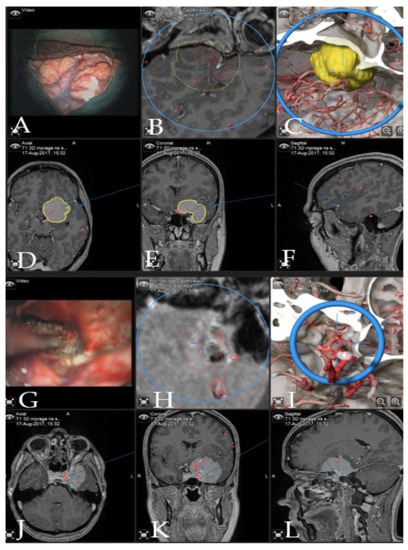

Case 1: Patient no. 28 was a 77-year-old female patient with right clinoidal meningioma who experienced visual field deficits and visual deterioration. A complete resection of the tumor was performed via right fronto-temporal craniotomy. AR support facilitated the course of the resection with prompt localization of the segmented carotid and cerebral arteries, as well as the optic chiasm, providing surgical precision throughout the procedure. Figure 3 demonstrates navigation and AR support at the beginning of the tumor resection and Figure 4 shows the microscopic view following the gross total resection of the tumor. The patient recovered fully and was neurologically intact. Operative video has been added to Supplementary Materials: Video Pt 28.

Figure 3. Navigation and AR support during surgery (patient no. 28). (A) Microscope video with head-up display and 3-dimensional (3D) visualization of the segmented objects (tumor in yellow, carotid and anterior cerebral arteries in blue, optic chiasm in yellow). (B,C) Probe’s eye view in 2D and 3D mode. Navigation display in (D) axial, (E) coronal and (F) sagittal view with the segmented objects (focus on the tumor following debulking). (G) AR display on video screen with the 3D outline of tumor, carotid arteries, optic nerves and chiasm. (H) Corresponding probe’s eye view. (I) Target view (tumor and further objects outside of the focus plane are visualized) and (J) video plane in relation to the 3D objects.